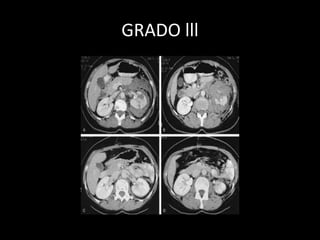

GRADO lll

GRADO IV

• 90% Tratamiento conservador